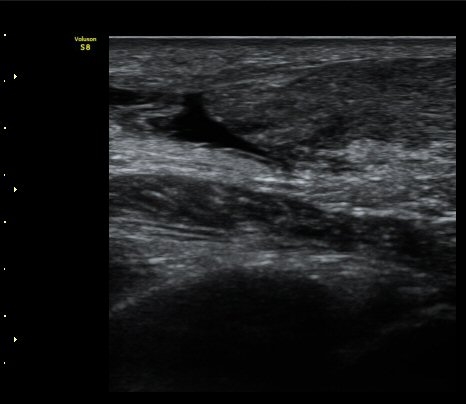

[¹ß¸ñ] ¾ÆÅ³·¹½º ÈûÁÙ ÆÄ¿­ÀÇ ÃÊÀ½ÆÄ Áø´Ü

ÁÂÃø ¹ß¸ñÀÇ ÅëÁõ(2ÁÖ)

2ÁÖ Àü ¹èµå¹ÎÅÏÇÏ´Ù°¡ ¹ß¸ñÀÇ ÅëÁõÀÌ ¹ß»ýÇÏ¿© Ÿº´¿ø¿¡¼­ ÃÊÀ½ÆÄ°Ë»ç µî ½ÃÇàÇÏ°í ºÎ¸ñ°íÁ¤ ÈÄ ¹°¸®Ä¡·á À§ÇØ ³»¿ø

¾ÆÅ³·¹½º°Ç ºÎÁ¾ ¹× ¾ÐÅë, ´Éµ¿Àû ¹ß¸ñ ¹ß¹Ù´ÚÃø ±¼°ñ G 1, thomson test(+).

ÃÊÀ½ÆÄ °Ë»ç

¼ö¼ú Ä¡·á À§ÇØ Àü¿ø